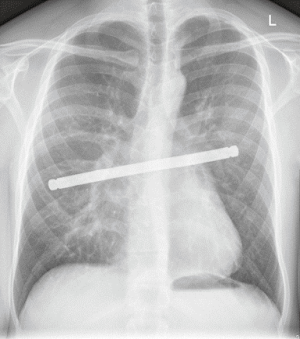

More frequently chest wall reconstruction is required for peripheral lung cancer invading lateral aspects of the chest wall. In this situation absent ribs also could be replaced by various forms of titanium bars, such as titanium Stratos bars (MedXpert, Germany) which are available in different size and could be also trimmed according to the individual need (Figure 3). If the muscle defect over the bars is significant, overlying Prolene mesh may be helpful to prevent lung herniation in the postoperative period.